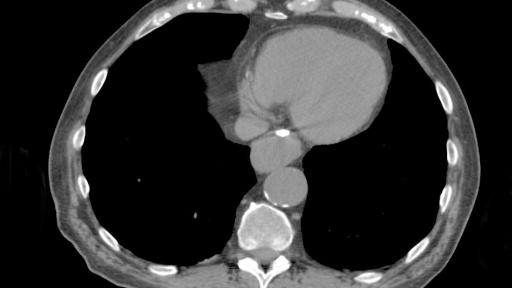

BioXmark® (1mL) is indicated for use to radiographically mark soft tissue in or adjacent to malignant tissue in the thoracic region during a surgical procedure for at least two months after placement. BioXmark® is injected via very thin needles (endoscopically or percutaneously) and provides visibility of the target throughout the treatment. It is biodegradable and is completely resorbed within a few years.

BioXmark® is visible on x-ray, CT, CBCT, fluoroscopy, MRI and ultrasonography enabling multi-modality image-guided planning and treatment, which is becoming the standard treatment approach in radiotherapy in hospitals across Europe. Compared to conventional metal based soft tissue markers, BioXmark® creates limited artefacts in CT and MRI and induces minimal dose perturbation in proton therapy. Moreover, BioXmark® has no sharp edges, which tend to cause migration of conventional metal based markers in patients.

"We have tested BioXmark® in patients with lung cancer and found that it is easy to work with and clearly visible. Markers were injected in tumour tissue, lymph nodes and lung tissue and we observed no migration from the planning CT to end of treatment ,” said Lena Specht, MD, PhD, Professor of Oncology, Dept. of Oncology, Rigshospitalet, Copenhagen University Hospital, Denmark. “ We have also tested BioXmark® in patients with oesophageal cancer and saw no migration between planning CT to end of treatment, and again, BioXmark® was well tolerated."